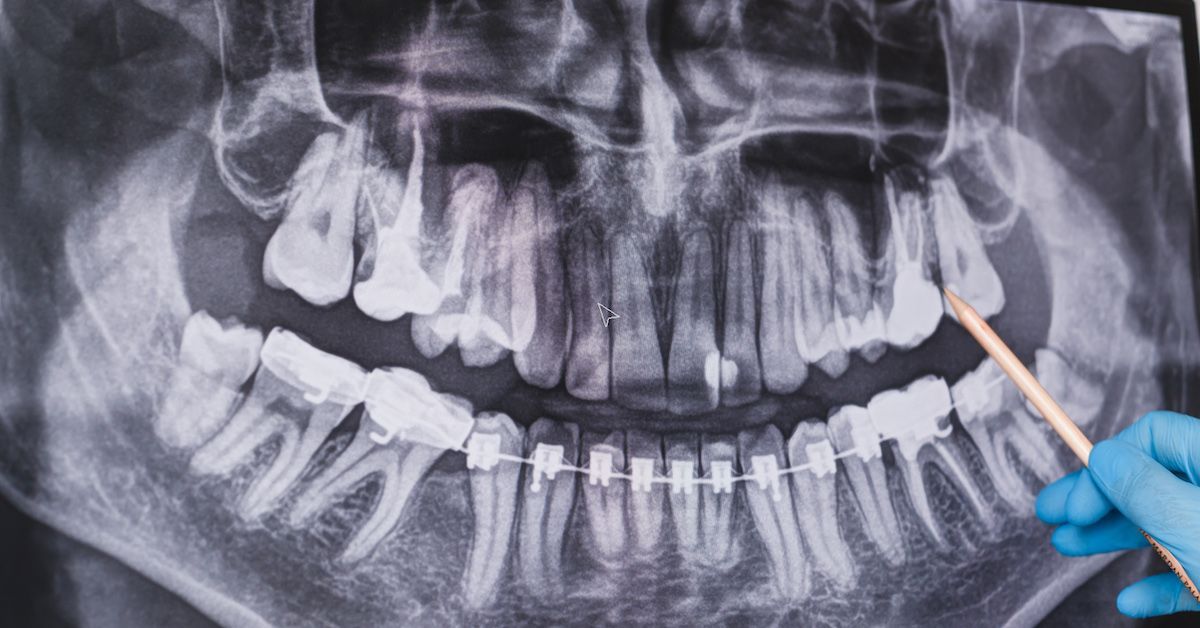

Een panoramische röntgenfoto, ook wel een orthopantomogram genoemd, is een van de meest gebruikte röntgenfoto’s in de tandheelkunde. Deze opname geeft een overzichtsbeeld van het hele gebit en de kaken, waardoor de tandarts problemen kan opsporen die bij een gewoon mondonderzoek niet zichtbaar zijn.

Bij dit onderzoek wordt een speciaal röntgentoestel gebruikt dat om het hoofd van de patiënt draait en zo een gedetailleerd beeld van de mond maakt.

Met een panoramische röntgenfoto kunnen de tanden, de boven- en onderkaak en de omliggende botstructuren in één opname in beeld worden gebracht.

De tandarts kan hiermee verschillende aandoeningen opsporen, zoals problemen met tandwortels, ontstekingen (abcessen) en in zeldzame gevallen tumoren.

Dit onderzoek wordt vaak uitgevoerd vóór de start van een orthodontische behandeling.

Ook wanneer een patiënt zijn of haar gebit wil verbeteren, kan de tandarts met behulp van een panoramische röntgenfoto onder andere cariës, niet-doorgebroken verstandskiezen, kaakbreuken en ontwikkelingsafwijkingen van de tanden vaststellen.